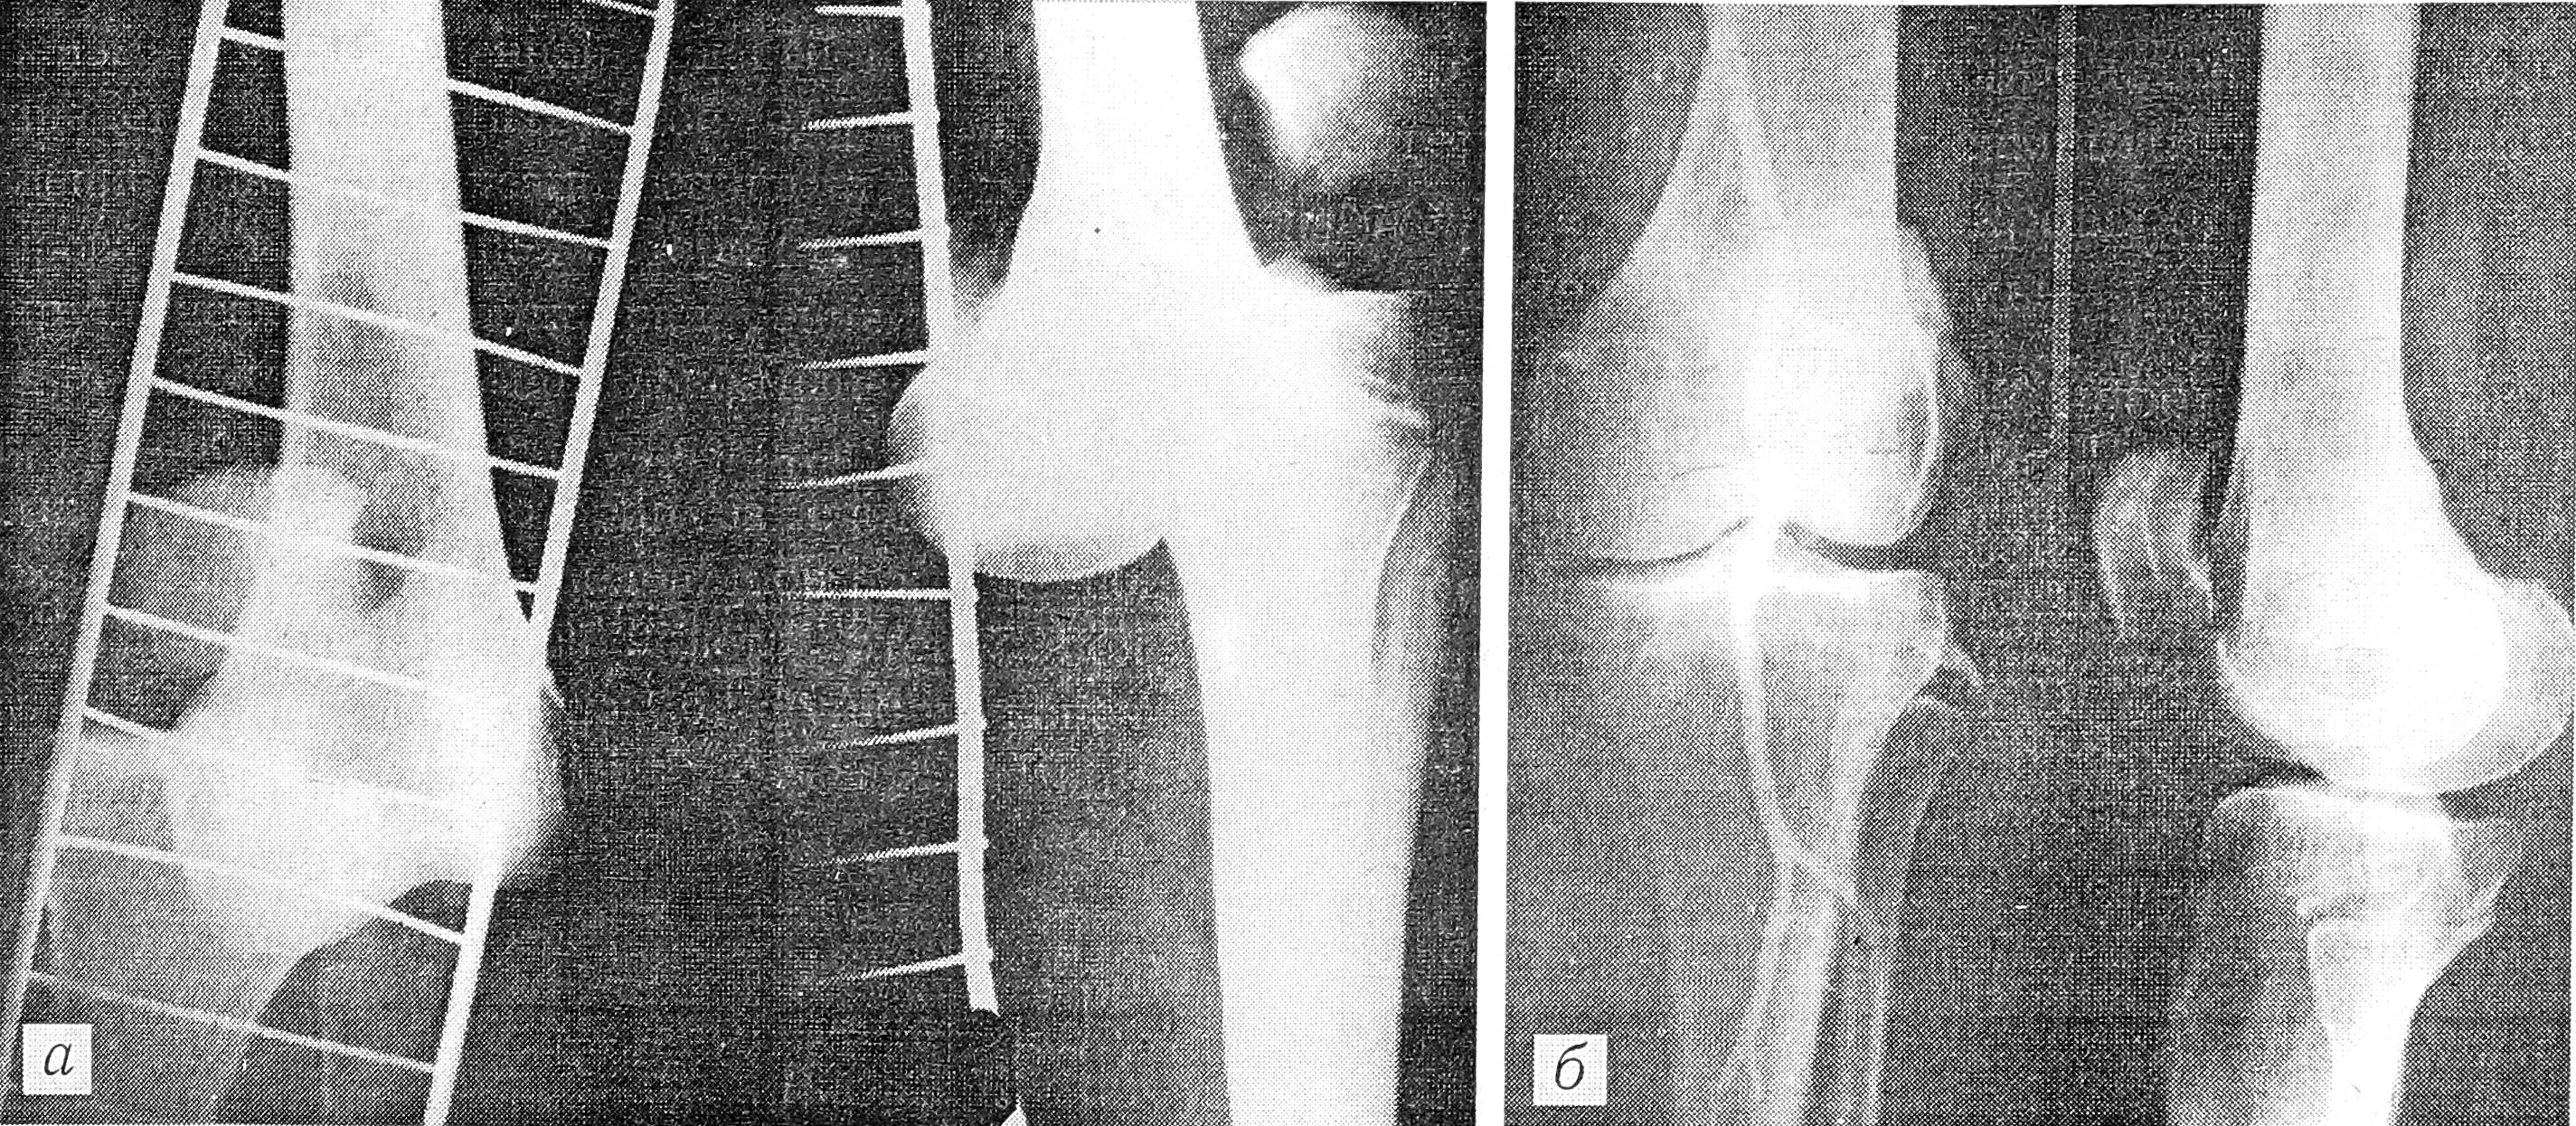

В качестве примера приводим одно из наблюдений.

Больная К., 37 лет, поступила в больницу через 2,5 ч после травмы. Диагноз: открытый полный передний вывих левой голени, разрыв подколенной артерии и вены (см. рисунок, а), две обширные раны — в подколенной области и на бедре. Произведены безотлагательное одномоментное вправление вывиха, фиксация спицами, временное шунтирование подколенной артерии (4 ч), первичная хирургическая обработка ран, ревизия сосудов, нервов, фасциотомия 4 фасциально-мышечных футляров, шов большеберцовой связки, аутовенозная пластика подколенной артерии за счет большой подкожной вены здорового бедра, шов подколенной вены конец в конец. Через 9 лет: артерия полностью проходима (см. рисунок, б), функция конечности нормальная. Работает по-прежнему бетонщицей. Исход расценен как отличный.

Рентгенограммы больной К. при поступлении (а) и через 9 лет после травмы (б).